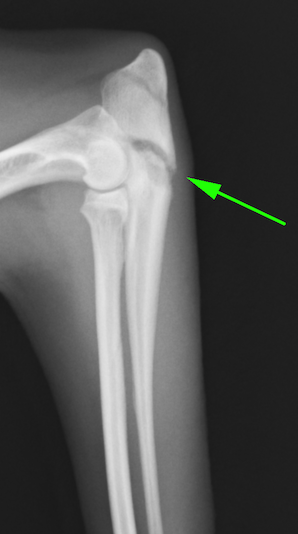

今回紹介するのは30cmほどの高さから降りたときに着地に失敗し、そこから前足を痛がっているという8ヶ月の柴犬です。すぐに近くの病院に行き痛み止めを処方されたのですが、3週間経っても良くならない、足を痛がっているとのことで来院されました。レントゲン画像検査では左の肘頭の骨折、3週間経っているのに骨がくっついていない(通常この年齢であれば3週間経つと骨が着きだします)ため、癒合不全と呼ばれる状態と判断しました(偽関節)。癒合不全は骨がくっつくことを諦めてしまい、そのまま骨が萎縮していってしまうことを言います。放っておくと骨が肉芽線維に置換され足を着けなくなってしまう子もいます(ひどいと断脚することもあります。。。)。

矢印の部分が骨折線です。通常であれば架け橋のような骨が出てくる時期ですが、それが全くありません。おそらく骨折部位が常にグラグラとしているため骨が生着する余裕がないためです。